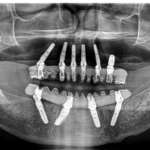

Dall’anamnesi al successo implantare

Grazie ad Alfred l’odontoiatra può conoscere le caratteristiche e la storia clinica di ogni paziente, in qualsiasi momento e con estrema precisione. Questo consente di avere il panorama completo di ciascun caso clinico e di valutare adeguatamente le scelte terapeutiche da attuare nelle varie circostanze. La migliore premessa per il successo di un intervento di riabilitazione implanto-protesica.

Dai “big data” al singolo paziente: Alfred, il maggiordomo intelligente

La prima piattaforma con intelligenza artificiale “cloud based” che dialoga con tutti gli utilizzatori di TMM3, il motore per inserimento implantare IDI EVOLUTION, ed esamina i numerosissimi dati a sua disposizione alla ricerca di pattern che possano orientare il singolo implantologo nella pratica quotidiana e il ricercatore nella pianificazione di studi clinici.